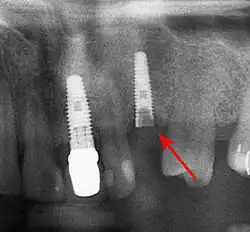

Bone loss (peri-implantitis) on implants over 7 years in a heavy smoker

Screw fracture

Fracture of abutment screws (arrow) in 3 implants required removal of the remainder of the screw and replacement.